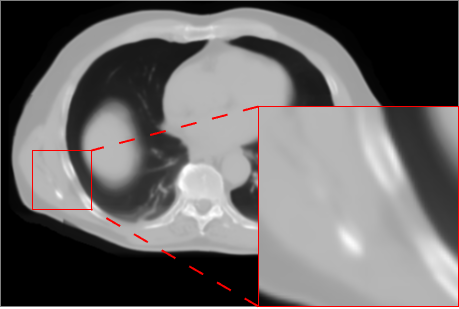

6.2 CBCT to CT translation (Task 2)

Figure 3 presents qualitative results for the CBCT-to-CT translation task on the HN dataset. The displayed axial slices include a lesion visible inside the brain, allowing a focused assessment of reconstruction quality. Visual inspection shows that AFP-based models generally produce slightly sharper and more accurate reconstructions than L1-only models, with nnResU-Net providing the most precise delineation. In particular, the combination of AFP with nnResU-Net better reconstructs the lesion compared to other configurations.

![]() |

| Input CBCT | nnU-Net L1 | nnU-Net L1 + AFP |

| Real CT | nnResU-Net L1 | nnResU-Net L1 + AFP |

Quantitative results in Table 5 and Table 6 are computed on the fused HN, AB, and TH datasets. As observed for Task 1, intensity-based metrics are best for nnResU-Net with L1 loss, reflecting the direct optimization of pixel-wise MAE, PSNR, and MS-SSIM. Conversely, segmentation-based metrics show a clear advantage for AFP, with nnResU-Net + AFP achieving the highest DICE and lowest HD95, in line with visual observations of more accurate anatomical boundaries and lesion reconstruction. Overall, the trends across models and losses are consistent with Task 1, confirming the benefits of AFP for improving structure-level fidelity without necessarily maximizing intensity-based metrics.